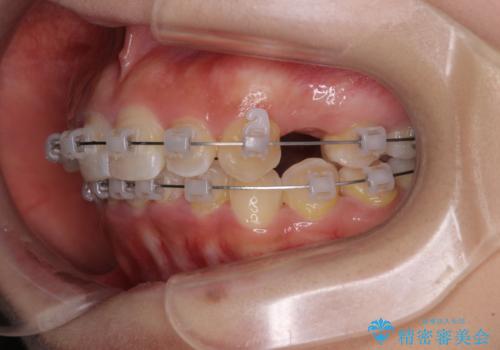

- クリアブラケット

- 上顎の八重歯と、上下前歯のデコボコを気にして来院された患者様です。

奥歯の咬み合わせを見ると、上顎臼歯が下顎に対して前方にあり、叢生改善により口元が突出する顔貌ではなかったため、上顎左右第一小臼歯2本を抜歯し、ワイヤー装置にて矯正治療を行うこととしました。

前歯部のデコボコがなくなったため、歯磨きしやすくなり、非常に清潔な状態になりました。